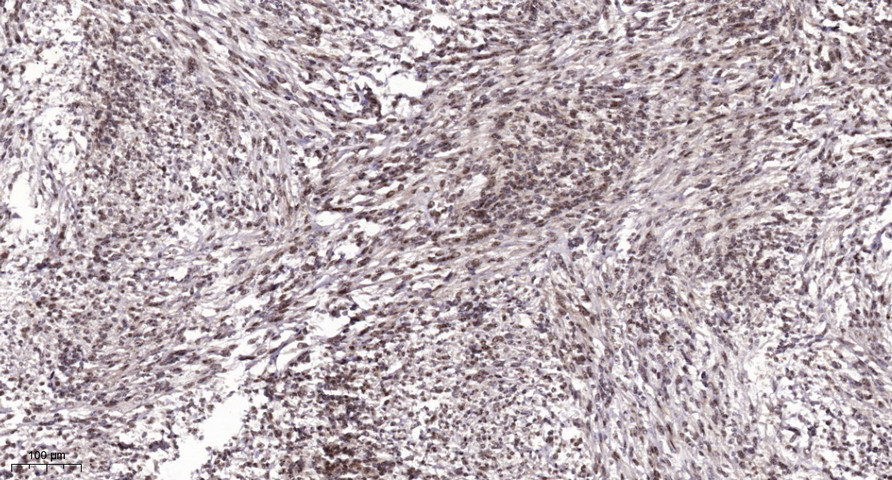

Main InformationTargetCENPMHost SpeciesRabbitReactivityHuman, MouseApplicationsIHC, IF, WBMW20kD (Observed)Conjugate/ModificationUnmodifiedDetailed InformationRecommended Dilution RatioIHC 1:50-200; WB 1:500-2000; IF 1:50-200FormulationLiquid in PBS containing 50% glycerol, 0.5% BSA and 0.02% sodium azide.SpecificityThis antibody detects endogenous levels of human CENP-MPurificationThe antibody was affinity-purified from rabbit antiserum by affinity-chromatography using epitope-specific immunogen.Storage-15°C to -25°C/1 year(Do not lower than -25°C)Concentration1 mg/mlMW(Observed)20kDModificationUnmodifiedClonalityPolyclonalIsotypeIgGAntigen&Target InformationImmunogen:Synthesized peptide derived from human CENP-M AA range: 30-110Specificity:This antibody detects endogenous levels of human CENP-MGene Name:CENPM C22orf18 ICEN39 PANE1Protein Name:CENP-MOther Name:Centromere protein M ; CENP-M ; Interphase centromere complex protein 39 ; Proliferation-associated nuclear element protein 1 ;Background:The protein encoded by this gene is an inner protein of the kinetochore, the multi-protein complex that binds spindle microtubules to regulate chromosome segregation during cell division. It belongs to the constitutive centromere-associated network protein group, whose members interact with outer kinetochore proteins and help to maintain centromere identity at each cell division cycle. The protein is structurally related to GTPases but cannot bind guanosine triphosphate. A point mutation that affects interaction with another constitutive centromere-associated network protein, CENP-I, impairs kinetochore assembly and chromosome alignment, suggesting that it is required for kinetochore formation. Alternative splicing results in multiple transcript variants. [provided by RefSeq, Jan 2015],Function:Function:Component of the CENPA-NAC (nucleosome-associated) complex, a complex that plays a central role in assembly of kinetochore proteins, mitotic progression and chromosome segregation. The CENPA-NAC complex recruits the CENPA-CAD (nucleosome distal) complex and may be involved in incorporation of newly synthesized CENPA into centromeres.,subcellular location:Nuclear in non-confluent cells and cytoplasmic in confluent or dividing cells (By similarity). Localizes in the kinetochore domain of centromeres.,subunit:Component of the CENPA-NAC complex, at least composed of CENPA, CENPC, CENPH, CENPM, CENPN, CENPT and MLF1IP/CENPU. The CENPA-NAC complex interacts with the CENPA-CAD complex, composed of CENPI, CENPK, CENPL, CENPO, CENPP, CENPQ, CENPR and CENPS.,tissue specificity:Isoform 3 is highly expressed in spleen, and intermediately in heart, prostate and ovary. Isoform 3 is highly expressed in resting CD19 B-cells and B-lineage chronic lymphocytic leukemia (B-CLL) cells and weakly expressed in activated B-cells. Isoform 1 is selectively expressed in activated CD19 cells and weakly in resting CD19 B-cells.,Cellular Localization:Nucleus. Cytoplasm. Chromosome, centromere, kinetochore. Nuclear in non-confluent cells and cytoplasmic in confluent or dividing cells (By similarity). Localizes in the kinetochore domain of centromeres. .Tissue Expression:Isoform 3 is highly expressed in spleen, and intermediately in heart, prostate and ovary. Isoform 3 is highly expressed in resting CD19 B-cells and B-lineage chronic lymphocytic leukemia (B-CLL) cells and weakly expressed in activated B-cells. Isoform 1 is selectively expressed in activated CD19 cells and weakly in resting CD19 B-cells.